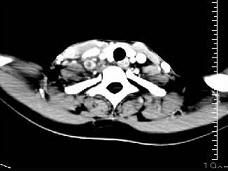

问题 女性35岁,发热、盗汗近3个月,颈部摸到多个结节,CT扫描如图所示,请选择最可能的诊断 ( )

选项 A、淋巴结核 B、淋巴瘤 C、结节病 D、淋巴转移癌 E、神经鞘瘤

答案 A